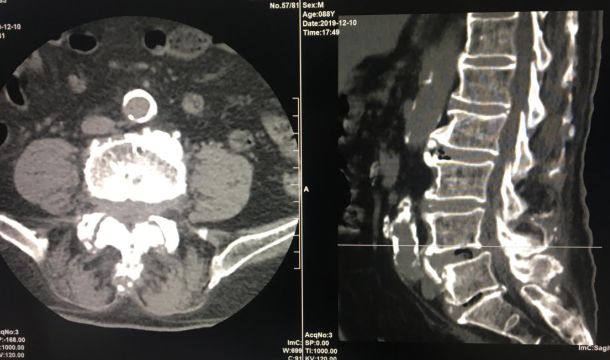

全新日本进口佳能金刚螺旋CT

该新设备功能先进,有平扫、三维重建、X线计算机体层成像等功能,能对人的头部、颈部、胸腔、四肢、盆腔等多个部位进行扫描成像。

现在医院引进了全新的进口螺旋CT,患者直接就能在医院确诊,节约了患者的时间,并且,进口的螺旋CT机扫描图像质量好,显示清晰。

腰椎椎间盘膨出伴双侧神经根受压

原发性肝癌伴骨转移

该设备自运行以来,发现并确诊不少疾病:颈椎椎间盘突出、 腰椎椎间盘膨出伴双侧神经根受压、硬膜外血肿、右侧上颌窦炎、右侧筛窦炎、双肺感染伴双侧胸腔积液、心包积液、右侧胸腔包裹性积液、原发性肝癌伴骨转移等疾病。